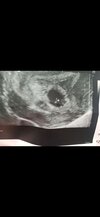

Jestem po drugiej wizycie. Oba jajowody są czyste, nic w nich całe szczęście nie ma. W macicy jest pęcherzyk ciążowy, ale za mały jak na ten wiek ciąży. Jest widoczny mały pęcherzyk żółtkowy. Więc albo ciąża dużo młodsza, ale coś jest nie tak